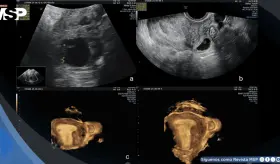

La mujer de 71 años, con antecedentes de histerectomía total y salpingooforectomía izquierda hace 30 años, presentó distensión abdominal progresiva y aumento de peso durante cuatro años.

Se confirmó un embarazo intrahepático de 23 semanas, una condición extremadamente rara en la que el feto se desarrolló dentro del lóbulo hepático derecho, con irrigación directa de la arteria hepática y una placenta firmemente adherida al tejido del hígado.